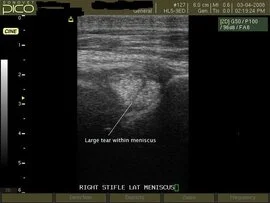

Image 2 An example of a diagonal tear running through the lateral meniscus of a lame horse.

In this image a large tear can be seen running diagonally across the lateral meniscus. This is a significant finding and one that would be consistent with a traumatic injury resulting in lameness. The horse was scheduled to undergo surgical exploration of the joint with arthroscopy.